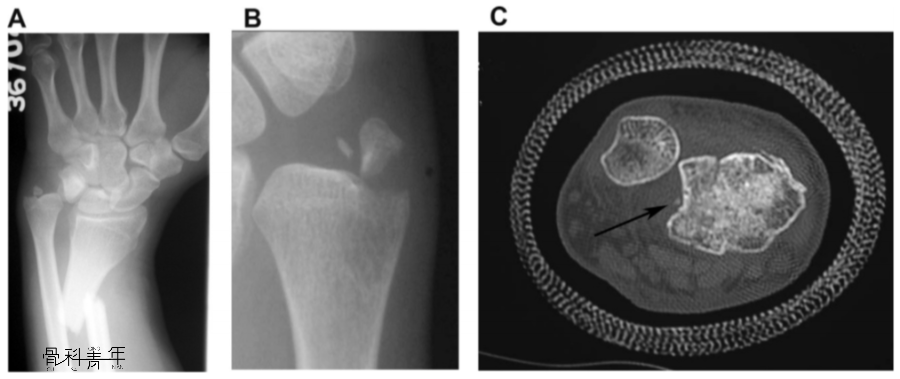

A:盖氏骨折;B:尺骨茎突基底部骨折;C:乙状切迹撕脱骨折

一例17岁患者,腕关节慢性疼痛3月,X线未见明显脱位(AB),MR检查提示下尺桡关节背侧脱位(C),予以下尺桡关节韧带重建(D),术后10年复查下尺桡关节位置良好,患腕无明显疼痛。